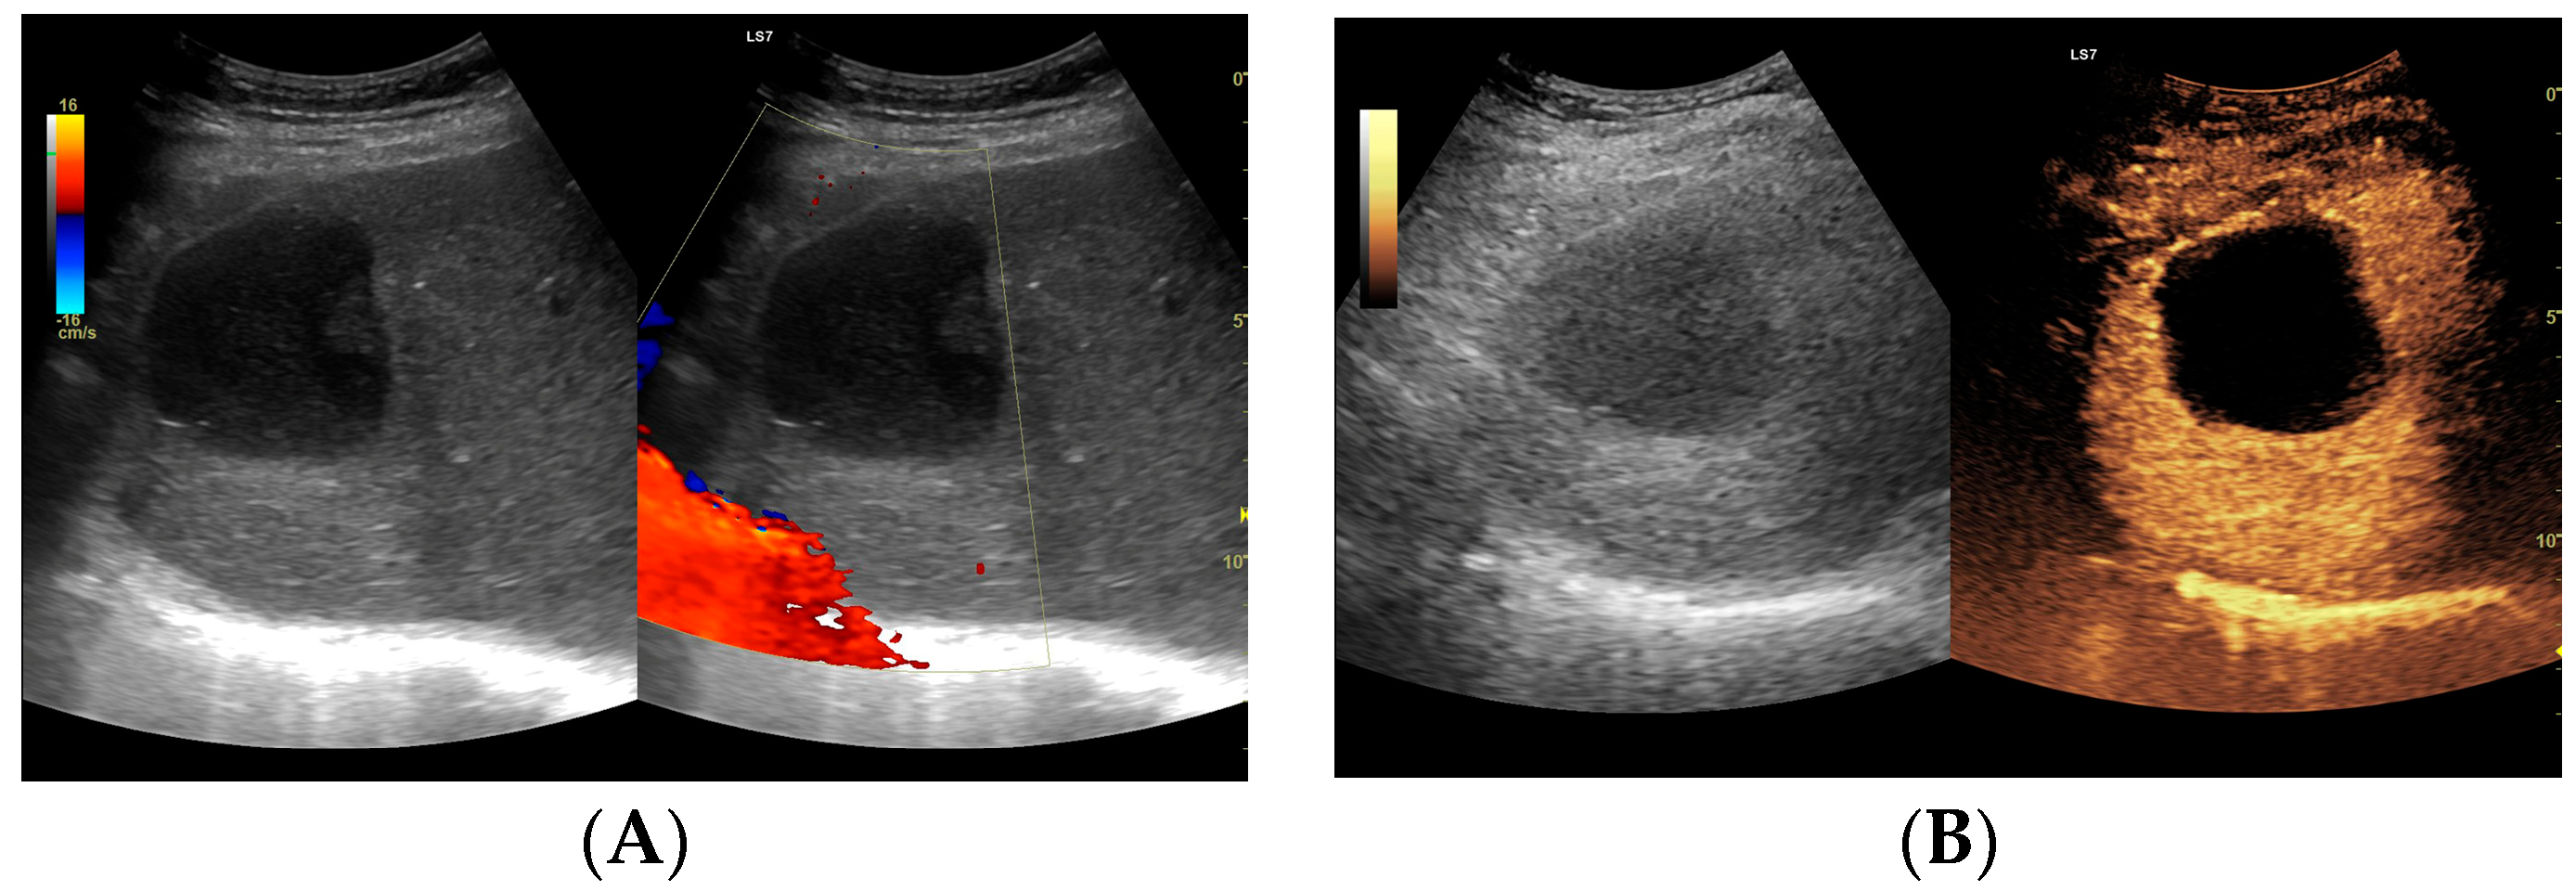

3.2.1. Arterial Phase

3.2.2. Early Venous Phase

3.2.3. Late Venous Phase